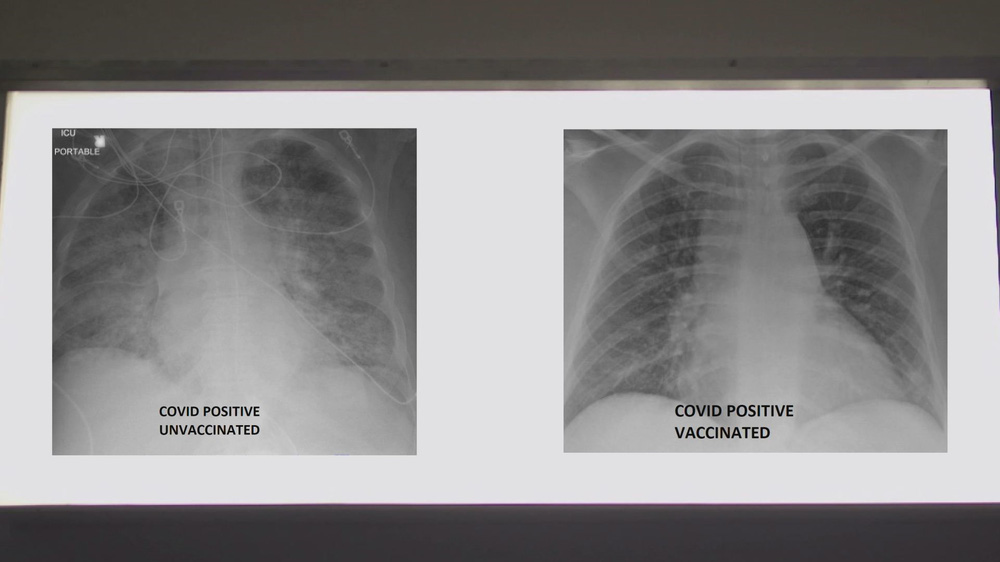

Một bác sĩ Mỹ vừa chia sẻ ảnh chụp phổi của 2 bệnh nhân COVID-19, nhấn mạnh về khả năng bảo vệ của vaccine COVID-19.

Để xem vaccine COVID-19 có thể giúp ích như thế nào, Bệnh viện SSM Health đã cung cấp hai bức ảnh chụp X-quang phổi của 2 bệnh nhân COVID-19 cho đài KSDK. Trong hai người này, một người đã được tiêm vaccine COVID-19, một chưa chưa tiêm.

Tiến sĩ Kamel đã xem phim chụp X-quang và giải thích chất màu trắng trong phổi mà bạn nhìn thấy chính là tác động của virus. Đó có thể là vi khuẩn, chất nhầy hoặc dịch tiết, tiến sĩ nói.

Tuy nhiên, tiến sĩ Kamel đã phân tích về sự khác biệt có thể thấy trên phim chụp X-quang.

Ông cho biết khi nhìn vào hình chụp X-quang của người chưa được tiêm vaccine COVID-19, ông đánh giá đây rất có thể một bệnh nhân cần được hỗ trợ.

"Họ chắc chắn ít nhất cũng cần oxy và đôi khi họ cần nhiều hơn thế. Họ có thể cần dùng máy thở hoặc được đặt nội khí quản, dùng thuốc an thần và về cơ bản là hỗ trợ sự sống", tiến sĩ Kamel nói.

Còn nếu bạn nhìn vào hình ảnh của người đã tiêm vaccine, bạn sẽ thấy nhiều màu đen hơn. Tiến sĩ Kamel giải thích: Khi phổi chứa đầy không khí, nó sẽ có màu đen trong phim X-quang. Như vậy, bức ảnh này có nhiều màu đen hơn ảnh trước.

Chủ nhân của phim X-quang này mắc COVID-19 dù đã được tiêm vaccine - một trường hợp hiếm khi xảy ra. Chỉ dưới 1% những người được tiêm vaccine bị nhiễm COVID-19.

Đối với những người đã tiêm vaccine mà không may nhiễm bệnh, họ thậm chí có thể không cần đến bệnh viện.

Nếu họ cần tới bệnh viện, hầu hết đều không cần phải vào ICU hoặc cần hỗ trợ sự sống, tiến sĩ Kamel cho biết. Các trường hợp ngoại lệ bao gồm những người có bệnh nền từ trước hoặc những người bị suy giảm miễn dịch.

So sánh ảnh chụp phổi của bệnh nhân COVID-19 không tiêm và có tiêm vaccine. Ảnh: KSDK